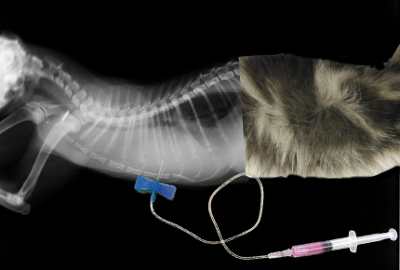

Es lo que llamamos una toracocentesis que consiste en introducir una aguja en la cavidad torácica del gato y aspirando mediante una jeringa, extraer tanto líquido como podamos.

Es una técnica que no está exenta de riesgos, pero es la forma más rápida de drenar los pulmones y que el gato pueda volver a respirar.

No existe un síntoma característico que permita diferenciar unas enfermedades de otras, los veterinarios hacemos el diagnóstico en base al historial, exploración del gato y ayudándonos de pruebas complementarias como los RX, análisis de sangre, del derrame e incluso tomando muestras del contenido de los propios bronquios y pulmones.